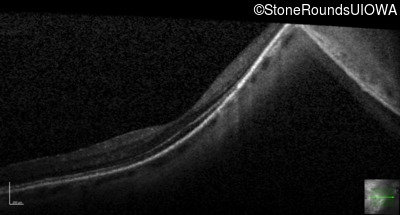

Infrared Fundus Photograph - Left - 20/25 +2

Exemplar